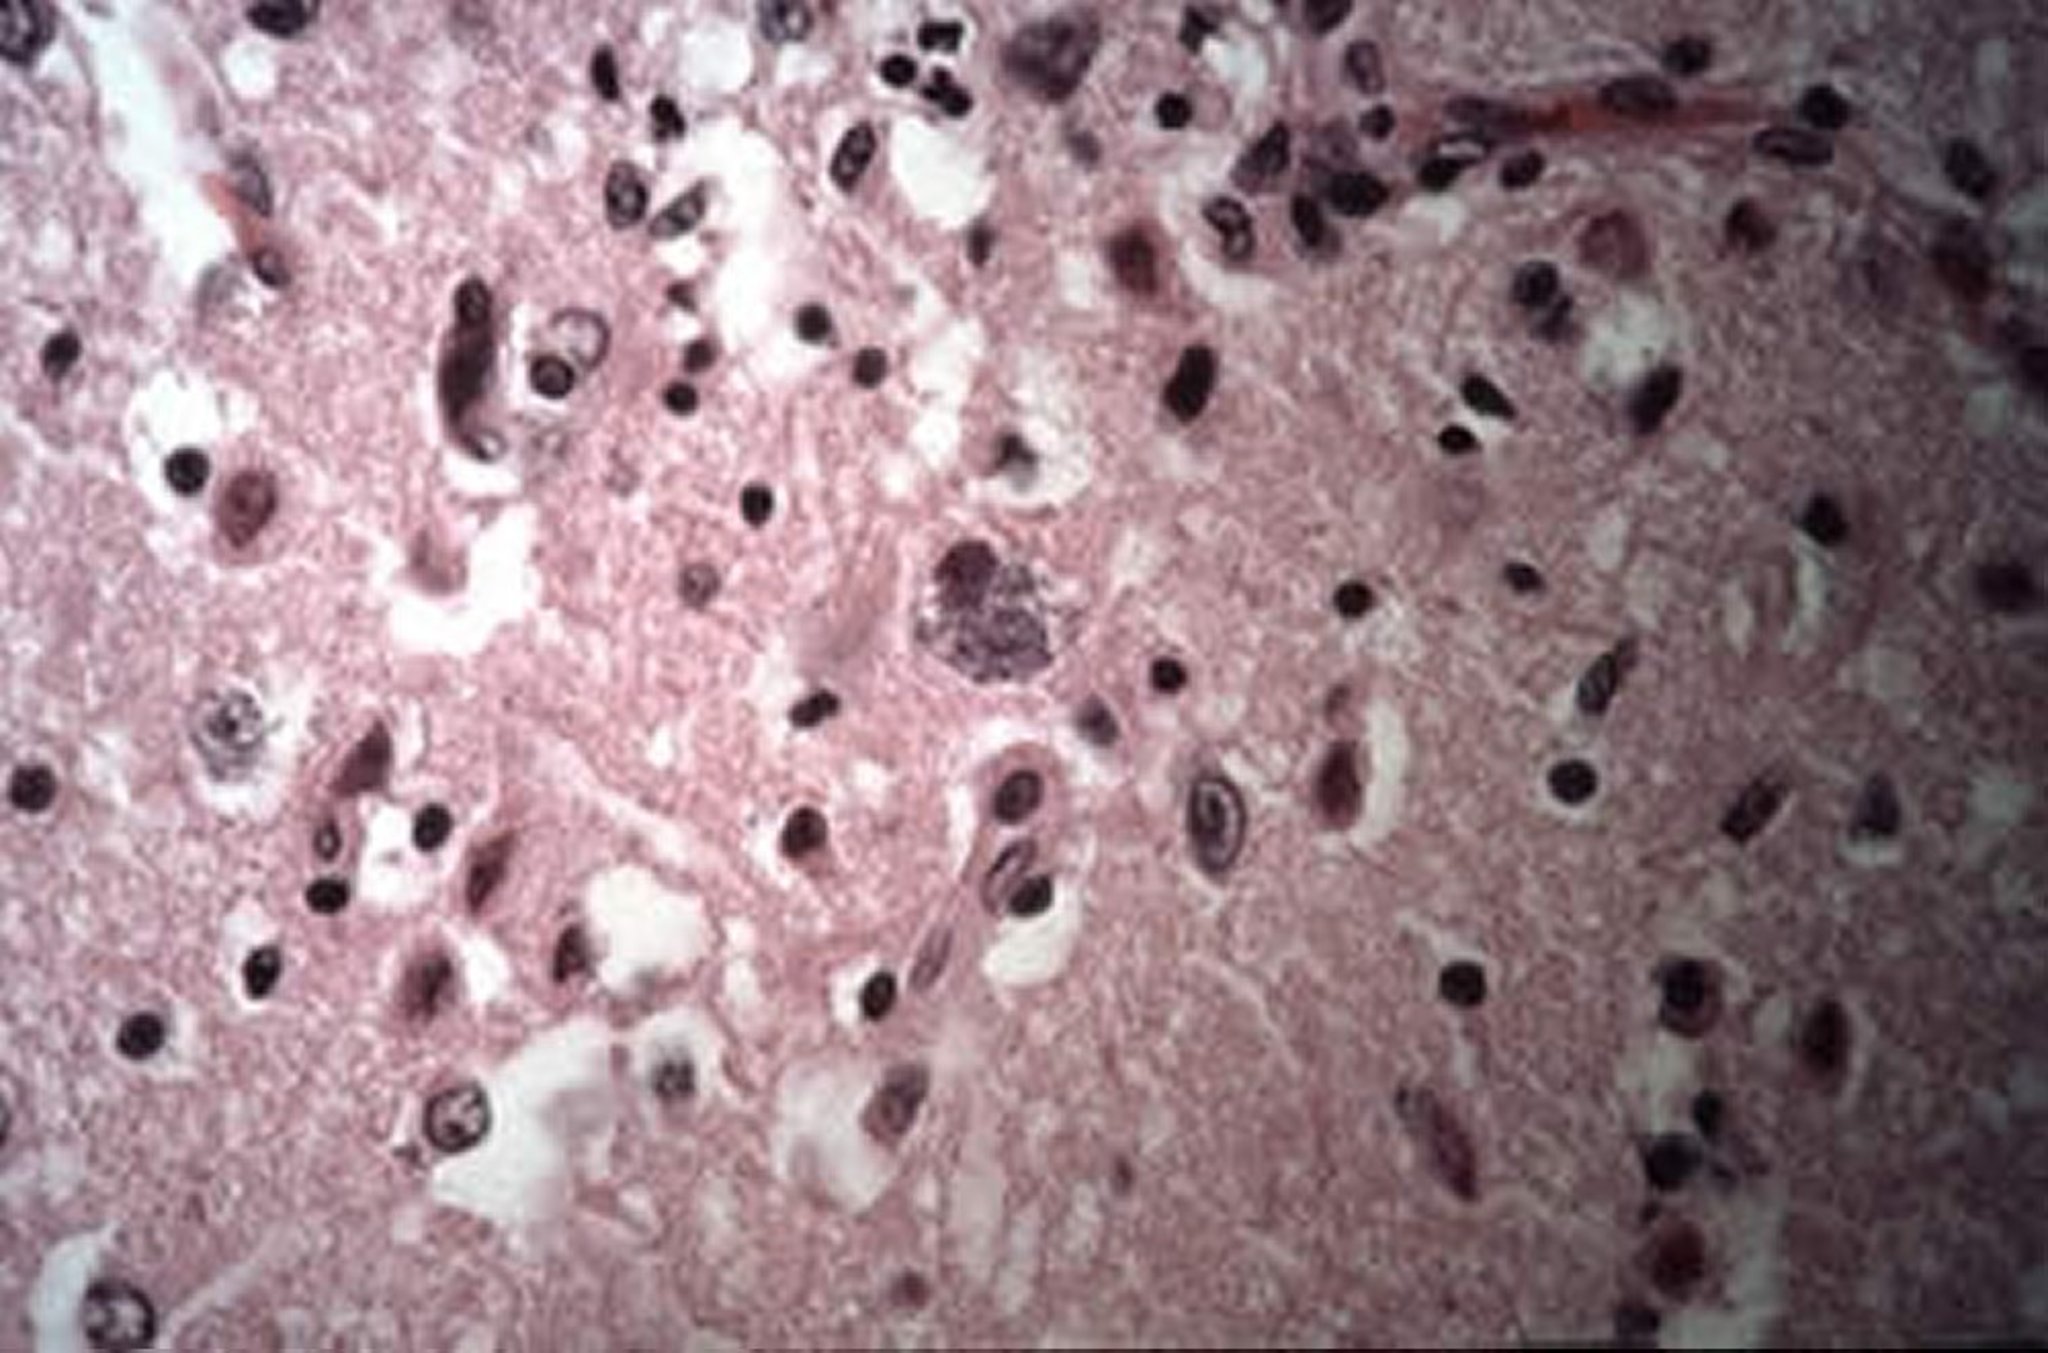

Intracellular cysts of Encephalitozoon cuniculi, brain, rabbit

Brain of a rabbit with intracellular cysts of Encephalitozoon cuniculi (H&E stain, 40X).

Courtesy of Dr. Tracy Bartick.